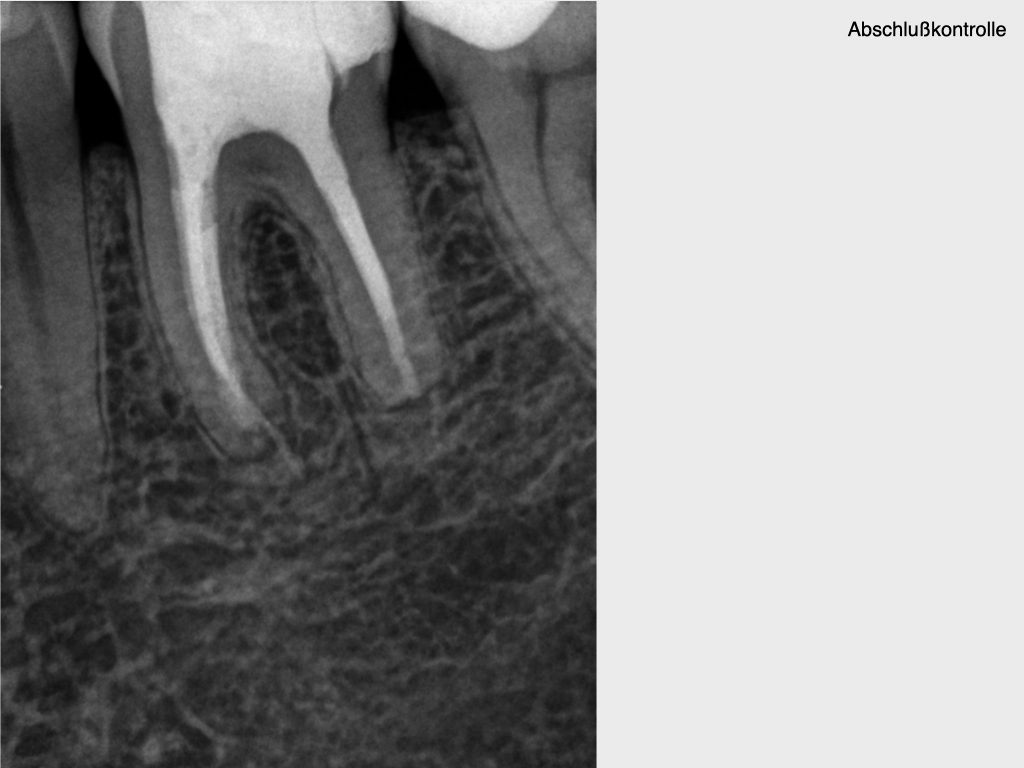

10 Jahres Recall